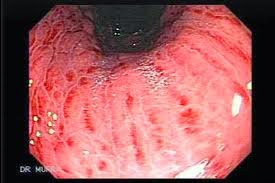

Namun, penelitian yang dilakukan oleh Dr Braden Kuo dari Rumah Sakit Umum Massachusetts, dapat membuat para penikmat mi instan berpikir ulang untuk kembali memakan mi. Dilansir dari laman Mercola, Ahad (25/1), berikut hasil yang mencengangkan dari penelitian Dr Kuo yang menggunakan kamera berukuran sangat mini untuk melihat apa yang terjadi dengan mi instan di dalam saluran pencernaan.

Mi instan tidak hancur dalam proses pencernaan berjam-jam

Mi instan, termasuk juga mie ramen asal Jepang, tidak hancur selama dua jam proses pencernaan di dalam tubuh. Bentuk mi yang masih utuh memaksa saluran pencernaan manusia bekerja ekstra keras untuk memecah makanan tersebut.

Jika mi instan tetap ada di dalam saluran pencernaan untuk waktu yang lama, akan sangat berdampak pada penyerapan nutrisi makanan lain. Selain itu, di dalam mi itu sendiri, tidak ada nutrisi yang bisa diserap tubuh. Sebaliknya, tubuh akan menyerap zat-zat aditif, termasuk zat beracun dari bahan pengawet, seperti tertiary-butyl hydroquinone (TBHQ).